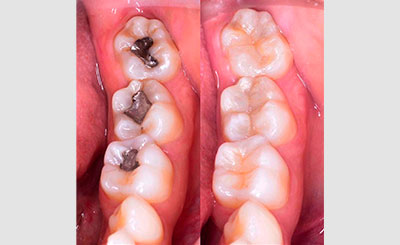

Fillings or restorations

Fillings or restorations..The composite filling will be precisely placed, shaped, and polished, restoring your tooth to its original shape and function.